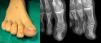

Su diagnóstico diferencial comprende un abanico de opciones relacionadas con la onicodistrofia, como la onicomicosis, la verruga plantar o la uña incarnata. La simple sospecha de una tumoración como origen de las alteraciones a nivel ungueal permite agilizar el diagnóstico y su tratamiento. Una radiografía simple en dos proyecciones ortogonales, donde se aprecia el sobrecrecimiento óseo, da el diagnóstico (fig. 1).